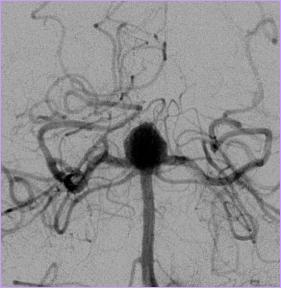

我的中文名字叫颅内动脉瘤,英文名字叫intracranial aneurysm

问我为什么正宗?因为我只是在颅内动脉管壁上的异常膨出啊!

你们人类有胖有瘦,就根据我们的形态分为囊性动脉瘤、梭形动脉瘤、夹层动脉瘤和不规则型动脉瘤

你们人类有自己的国籍,就根据我们发生部位可分为前循环动脉瘤和后循环动脉瘤